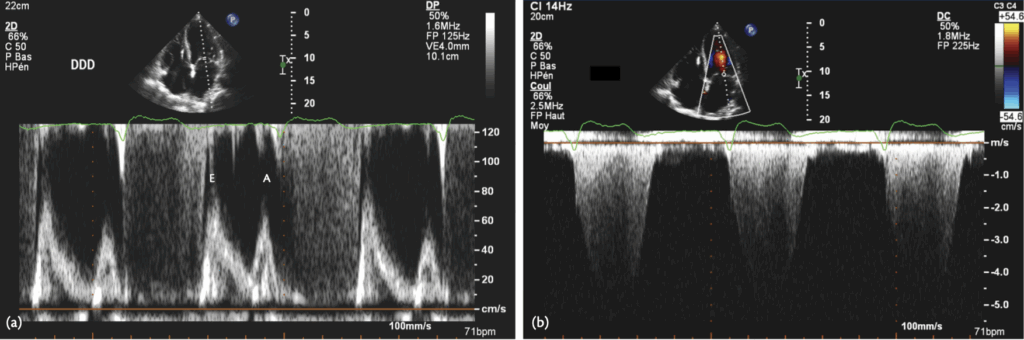

A 72-year-old patient was implanted with a dual-chamber pacemaker for sick sinus syndrome, programmed with the ADIR/DDDR algorithm. His LVEF was normal. The device counters indicated 96% AP and 2% VP. He complained of persistent dyspnoea. A real-time EGM is shown & transthoracic echocardiogram was performed, and the transmitral Doppler flow is shown here

P on T’

The ADI/DDD algorithm tolerates very long AVIs, which may, as in this case, lead to ‘P on T’, with atrial contraction occurring during ventricular systole, as in the pacemaker syndrome. The detrimental haemodynamic effect of RV pacing in the DDD mode needs to be balanced against improved AV synchrony. In this case, programming the pacemaker to the DDD mode revealed improved ventricular filling (below), with the appearance of an A-wave, as seen below. Also, diastolic mitral regurgitation was eliminated, although it probably was not the main cause of the patient’s symptoms.